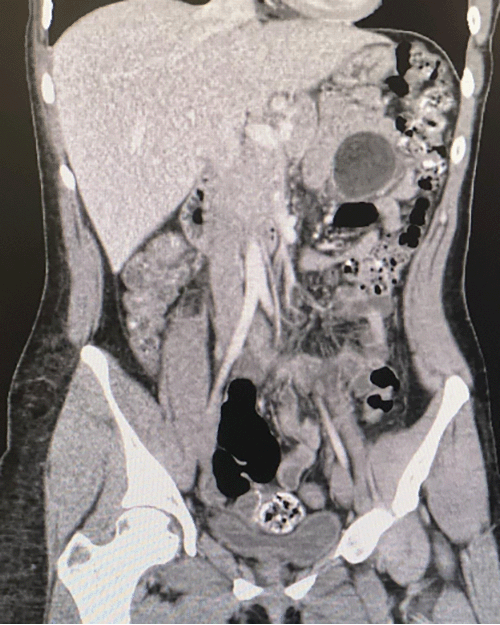

On admission, the patient was afebrile, normotensive, and in no respiratory distress, with oxygen saturation of 97% but was tachycardic to 105. Physical examination revealed a well-developed woman who appeared her stated age. The patient had a soft, nondistended, diffusely tender abdomen without rebound, guarding, or evidence of trauma. A complete blood count revealed a leukocytosis of 13.9 with a normal comprehensive metabolic panel. After a clinical exam and complete workup, the patient was thought to have a small bowel obstruction. With an inconclusive ultrasound (USG), she underwent radiographic evaluation via computed tomography (CT) imaging (Figure 1). CT revealed a LUQ mesenteric fat attenuating mass with mild adjacent mesenteric edema. A magnetic resonance imaging (MRI) was obtained (Figure 2) to evaluate the mass better, including the localization and features of the tissue, revealing an approximate 5 × 4 × 4 cm jejunal mesenteric mass most consistent with a mature cystic teratoma, with induration of surrounding mesentery.

Figure 2. MRI of Abdomen and Pelvis. Published With Permission

Scan demonstrating approximate 5 × 4 × 4 cm jejunal mesenteric mass most consistent with mature cystic teratoma, with induration of surrounding mesentery.